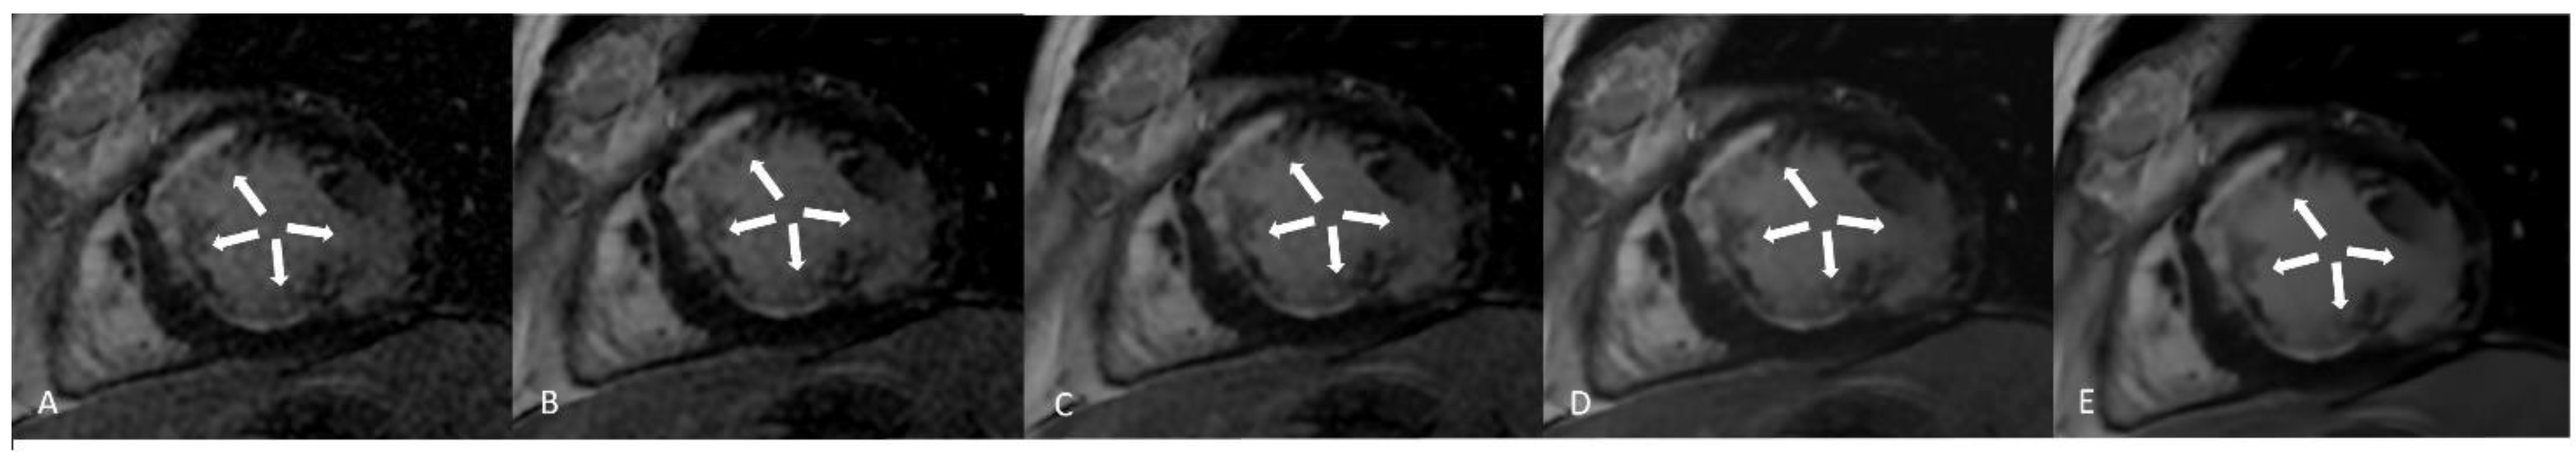

LGE sequences acquired using an artificial intelligence reconstruction deep learning algorithm. Forty-one-year old patient with previous myocardial infarction on anterior, anteroseptal, inferoseptal, inferior, and inferolateral segments (arrows, (A–E), respectively). Image noise decreased progressively with increase in AIRDL reconstruction in both 2D-SSLGE ((A): 2D-SSLGE AIRDL 0%, (B): 2D-SSLGE AIRDL 25%, (C): 2D-SSLGE AIRDL 50%, (D): 2D-SSLGE AIRDL 75%, (E): 2D-SSLGE AIRDL 100%). 2D-SSLGE—2D single segmented inversion recovery gradient echo late gadolinium enhancement sequences; AIRDL—artificial intelligence reconstruction deep learning.